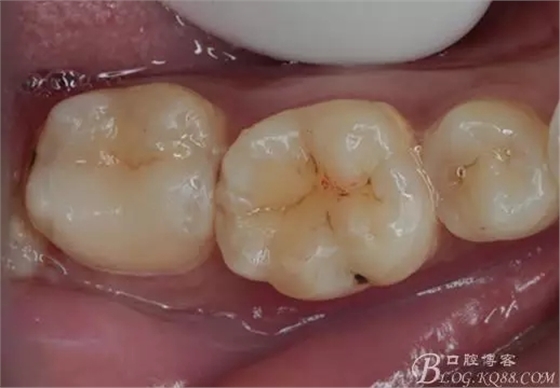

一周后復(fù)診,37臨時充填物完好。去除臨時充填物,清潔基牙,試戴嵌體,就位良好,邊緣密合。取下嵌體,常規(guī)處理,9.5%HF處理20S,沖洗一分鐘,95%酒精蕩洗5分鐘。基牙涂抹37%的磷酸凝膠,釉質(zhì)區(qū)域酸蝕30S,本質(zhì)區(qū)域15S。粘固用的是3M第八代粘接劑套裝,照說明書逐步操作。最終固化時涂滿阻氧劑,每個牙面最少光照30S,光固化燈用漸強模式。常規(guī)調(diào)合,配合硅膠尖套裝拋光。術(shù)后常規(guī)醫(yī)囑,不適隨診。

回訪:術(shù)后一周電話回訪無異常。